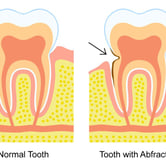

Desgaste dental (Abfracción)

La abfracción es la pérdida de esmalte dental en la región cervical del diente, generalmente causada por fuerzas oclusales excesivas.

Los pacientes pueden notar hendiduras o surcos en la base de los dientes. Esta condición puede causar sensibilidad y aumentar el riesgo de caries.

El tratamiento incluye ajustes oclusales y restauraciones dentales.